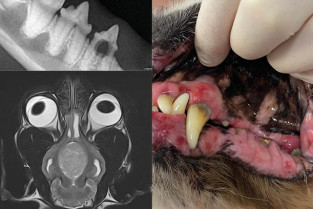

Les stomatites félines

Place de la radiographie, du scanner et de l'IRM dans l'imagerie de la face

Gestes de base en dentisterie